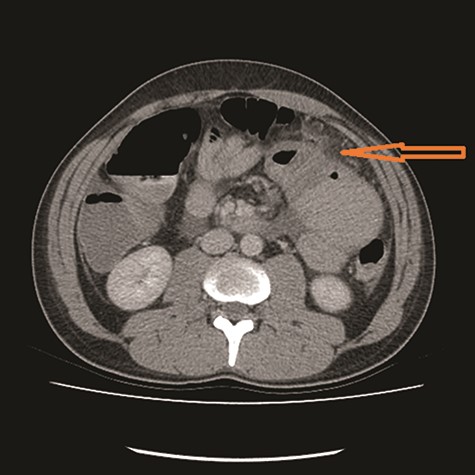

CT showed high-grade proximal jejunal obstruction secondary to a locally infiltrative jejunal mass (Fig. 1) suspicious for carcinoma. There was disseminated peritoneal carcinomatosis with a small volume of ascites and two hepatic metastases (Figs 2–4). A liver biopsy confirmed metastatic deposit of intestinal origin that was positive for CK20 and CDX2 and negative for CK7 and TTF1. There was a mutation in codon 61 of the NRAS gene with no sign of microsatellite instability. Diagnosis of jejunal adenocarcinoma was made.